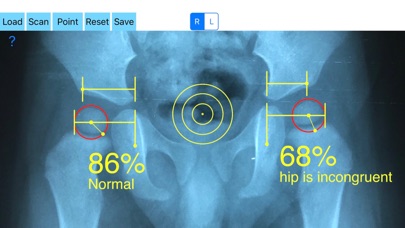

Treatment of incongruity is paramount importance because you have to address it early and the treatment of choice are usually corrective hip osteotomies. In order-from one hand to avert the natural course to the progression of secondary osteoarthritis (OA) and from another hand to avoid- in developing skeleton - to deteriorate more the hip dysplasia the congruity must be objectively and thoroughly evaluated especially at follow up of these procedures in both congruent and incongruent hips. Congruity between the femoral head and acetabulum is determined by the percentage of femoral head covered by the bony acetabulum. The congruity index (CI) is calculated (A/B- ratio converted to a percentage) by diving the (A) distance by the distance (B), where distance (A) is the distance between the teardrop to the lateral acetabular margin and (B) is the distance from the teardrop again to the lateral femoral head edge.

-Offers a very convenient way to determine the most accurate possibly way an objective value of congruity. By clicking three point at the x-ray picture on your iPhone screen and inserting the side the App calculates the congruity index (CI) which is the percentage of femoral head covered by the bony acetabulum. Congruity between the femoral head and acetabulum is expressed in percentage. Values of Coverage less than 75% is considered pathologic in another words the hip is incongruent